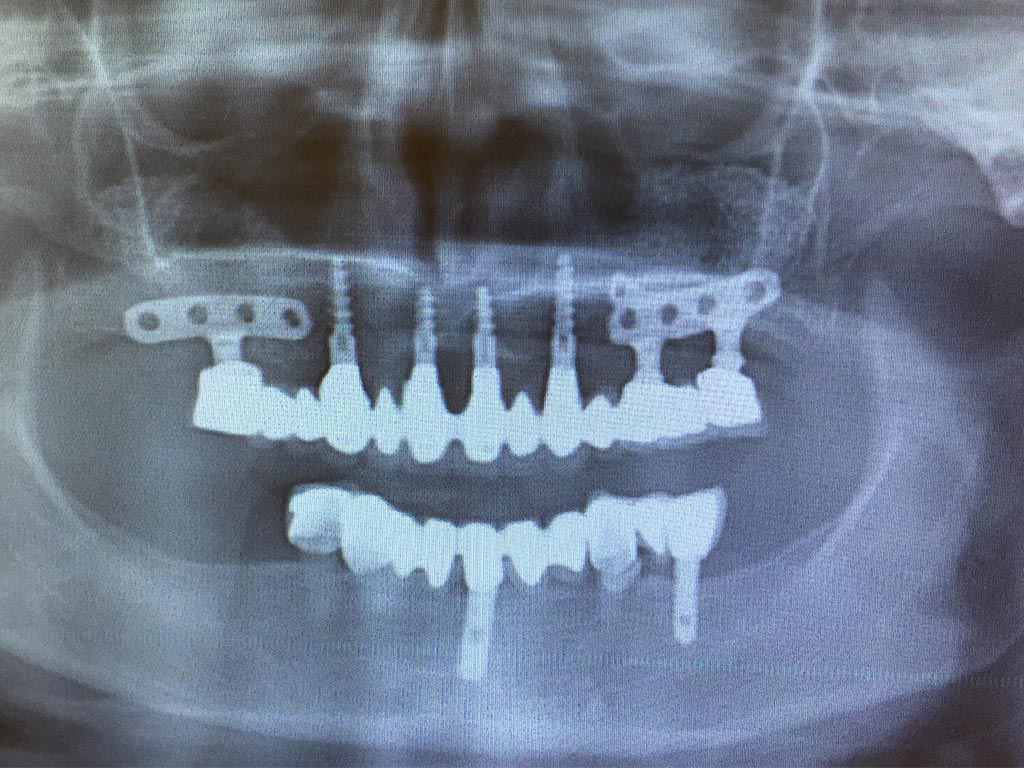

Teljes fogatlanság helyreállítása 2 nap alatt

Teljes fogatlanság helyreállítása 2 nap alatt azonnal terhelhető svájci IHDE implantátumokkal és PMMA műanyag hidakkal. Intraorális szkennerrel vettünk lenyomatot az implantáció után, és erre a digitális mintára készítette el a fogtechnika a hidak digitális tervezését, majd faragta ki műanyagból. Ezt a gyors munkát az azonnal terhelhető implantátumok és a digitális lenyomat, tervezés segítségével tudtuk megcsinálni mindössze 2 nap alatt. Dr. Kelemen Péter és a Symbion Fogtechnika munkája.